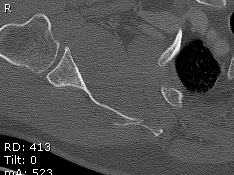

Combined Glenoid and Scapula Fractures

Case 1

- displaced glenoid fracture and neck fracture

- ORIF both through posterior / Judet approach